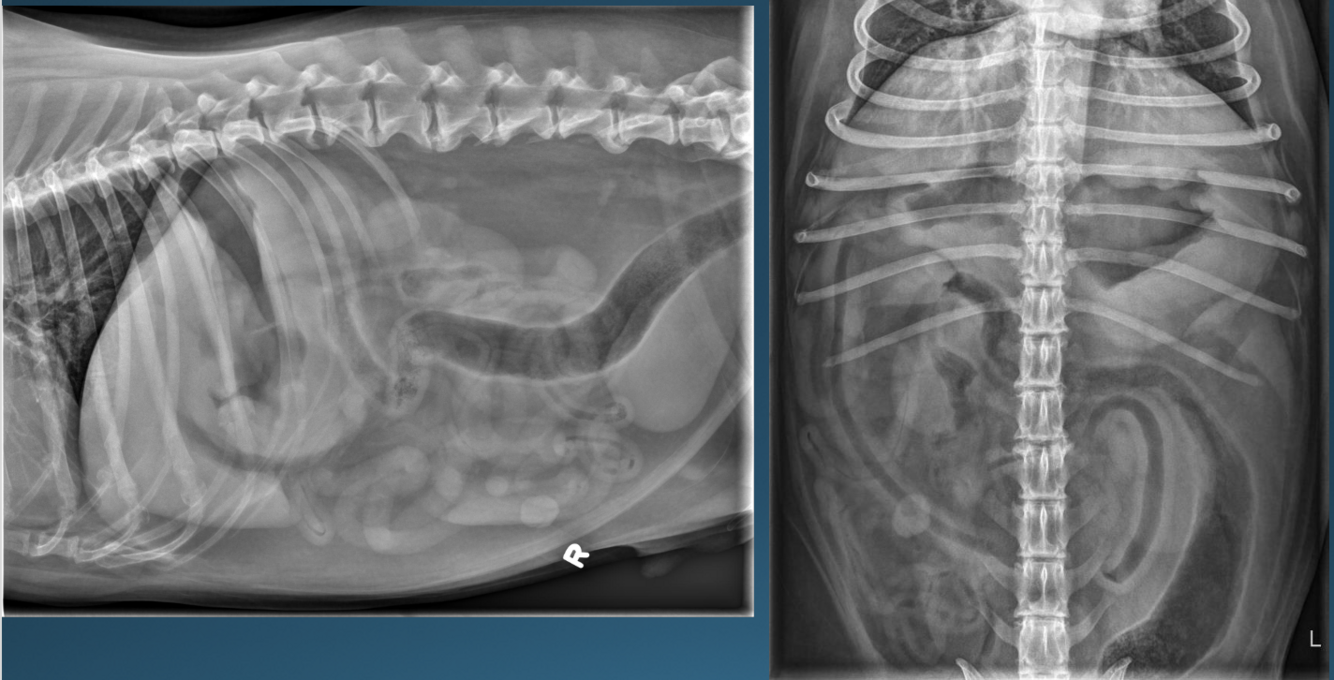

What is shown in these images?

A

gastric dilatation and volvulus

-“popeye arm” or “smurf hat”

-pylorus has moved dorsally and cranially; not seen well on VD view

-compartmentalization band seen

-pylorus is gas-filled on right lateral view

What are the imaging findings in acute gastric dilatation and volvulus?

*pylorus moves dorsally, cranially, and to the left

-greater curvature moves to right body wall

-may be accompanied by the spleen

*compartmentalization

-soft tissue band projected across lumen of the stomach; represents folding of distended organ

-can occur with GD or GDV

*small intestinal and esophageal dilation